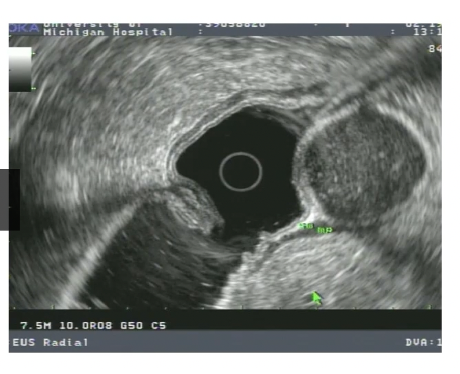

24

gastric duplication cyst